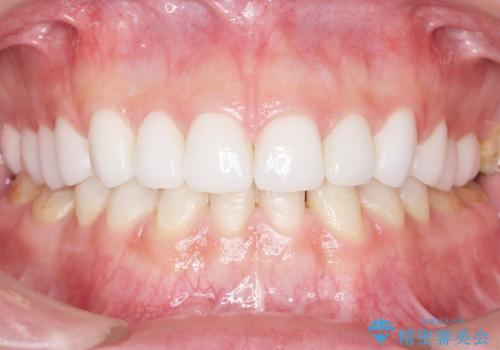

Kポップアイドルのような歯にしたい! 20代男性

- K-POP(Kポップ)アイドルのような歯にしたいと希望され来院された患者様です。

見た目と咬み合わせを改善するため、セラミッククラウンによる治療を行いました。

綺麗な仕上がりにご満足下さいました。

患者様の理想とする韓流アイドルの写真を技工士さんに送り、最終的なクラウンの形や色をできるだけ理想に近づけられるよう努めました。

クラウンの種類:オールセラミッククラウン スタンダード